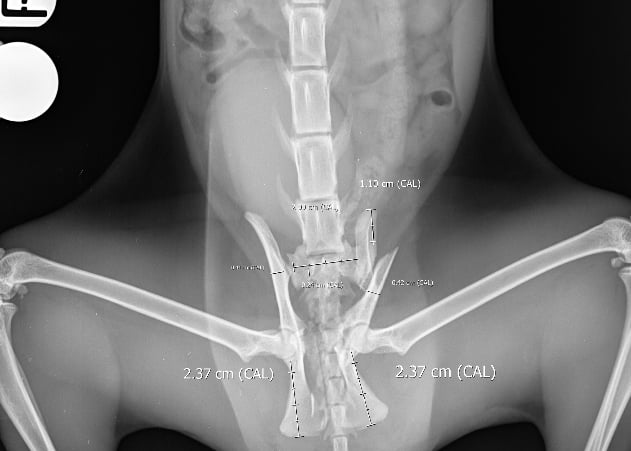

On presentation, she was unable to bear weight on her pelvic limbs. Withdrawal reflex and nociception were present, with normal proprioception in the right pelvic limb but delayed in the left. X-rays confirmed a right sacroiliac luxation, a left oblique ilium body fracture, a left ischium fracture involving the acetabulum, and bilateral pubic fractures (Figs. 1 and 2).

Fig. 2